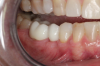

Fig 15. Provisionals 12 weeks postoperatively.

Figure 15

After the preparations were evaluated and accepted by the clinician, provisionals were completed with traditional crown-and-bridge techniques. Then the provisionals were fabricated with a replication stent derived from the diagnostic wax up (Figure 14). The provisionals were well-fitted to both the natural dentition and the ceramic dental implants (Figure 15). The provisional that was fixed to the implant was kept out of occlusion and had a narrow buccal-lingual occlusal table. The smaller occlusal table and short occlusal scheme provided light loading forces and stimulated the bone tissuethe brain detects the stimuli and sends osteoblasts to the area to increase bone density surrounding the implant. The recommendation for the light-loading provisional phase was to have the patient function with the provisionals for 4 weeks.